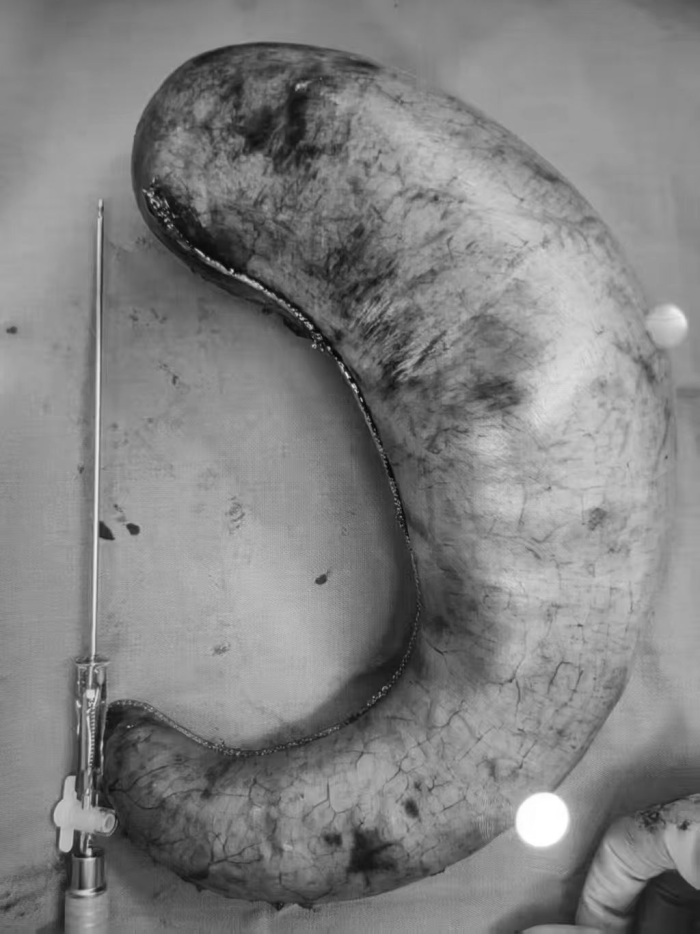

病例三:术中惊现“最大胃”,

手术重塑健康希望

下午的手术室里,团队按计划完成了一例“袖状胃+双通道”手术。术中,医护人员意外发现,这位患者的胃容量,是团队至今遇到的最大一例。

(图片已做色调处理)

当手术器械切除多余的胃组织、完成胃部重塑的那一刻,在场的每一位医护人员都深有感触:胃的形态可以通过手术重塑,但长期肥胖给身体带来的代谢损伤,却需要更长的时间、更科学的术后管理去慢慢修复。这台手术的顺利完成,也再次检验了我院肥胖与代谢外科诊疗协作组(减重代谢诊疗协作组)处理复杂病例的专业技术能力与协作水平。